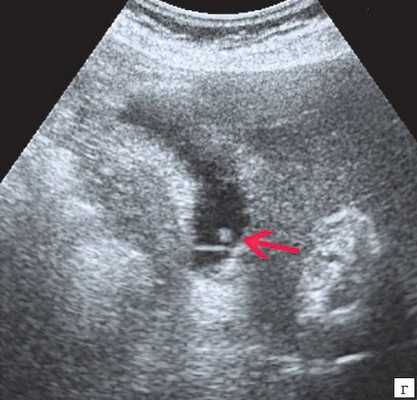

Материалы и методы. Исследование и лечение проводилось на базе детского хирургического стационара МУЗ ГКБ № 20 им. И.С. Берзона г. Красноярска, в котором проходили лечение 25 детей в возрасте от 1 мес. до 14 лет с врожденными кистами желчных протоков. При обследовании детей использовали клинико-лабораторную диагностику и инструментальные методы исследования: УЗИ в 100%, КТ - 50%, интраоперационная холецистография - 40%, ЭРХПГ -20%, лапароскопия - 20%. Эхографически киста общего желчного протока определялось как округлое или овальное анэхогенное образование, локализующееся в области головки поджелудочной железы и не связанное с желчным пузырем. Компьютерная томография полностью подтвердила данные, полученные при сонографическом исследовании. Следует отметить, что использование эндоскопической ретроградной холангиопанкреатографии позволяет выявить наиболее точную картину поражения общего желчного хода при сохранности проходимости в дистальной его части. На основании полученных данных решался вопрос о выборе метода хирургического лечения. Таким образом, дооперационная диагностика кистозной трансформации желчевыводящих путей в настоящее время значительно улучшилась благодаря применению современных методов исследования. Однако, выбор оперативного метода лечения окончательно может быть произведен только во время операции, так как решающее значение в верификации диагноза имеют интраоперационные рентгеноконтрастные методы исследования, которые позволяют выявить кистозные расширения вне- и внутрипеченочных желчных протоков, степень и протяженность их дилятации, проходимость терминального отдела холедоха, рубцовые сужения печеночных протоков, билиопанкреатический рефлюкс. В настоящее время предложен новый метод распознавания и лечения врожденной патологии желчевыводящей системы, включающий в себя комбинированное применение лапароскопии, чрезкожной чрезпеченочной холецистохолангиографии в сочетании с рентгенологическим контролем (под контролем электронно-оптического преобразователя) в режиме реального времени. К положительным сторонам данного метода относится: а) возможность применения у новорожденных детей; б) естественное (антеградное) введение контрастного вещества не допускает развития восходящего холангита; в) минимальная травматичность, г) высокая информативность, д) возможность в некоторых случаях устранять препятствие в области желчного протока.

Ультразвуковое исследование выполнено всем больным детям в 100%, что позволило в 60% поставить диагноз киста холедоха, КТ 7 детям (38%) с целью дифференциальной диагностики и уточнения топического расположения кисты, интраоперационная холецистография в 4 случаях (22 %), ЭРХПГ 3 пациентам (20%), лапароскопия 3 пациентам (20%).